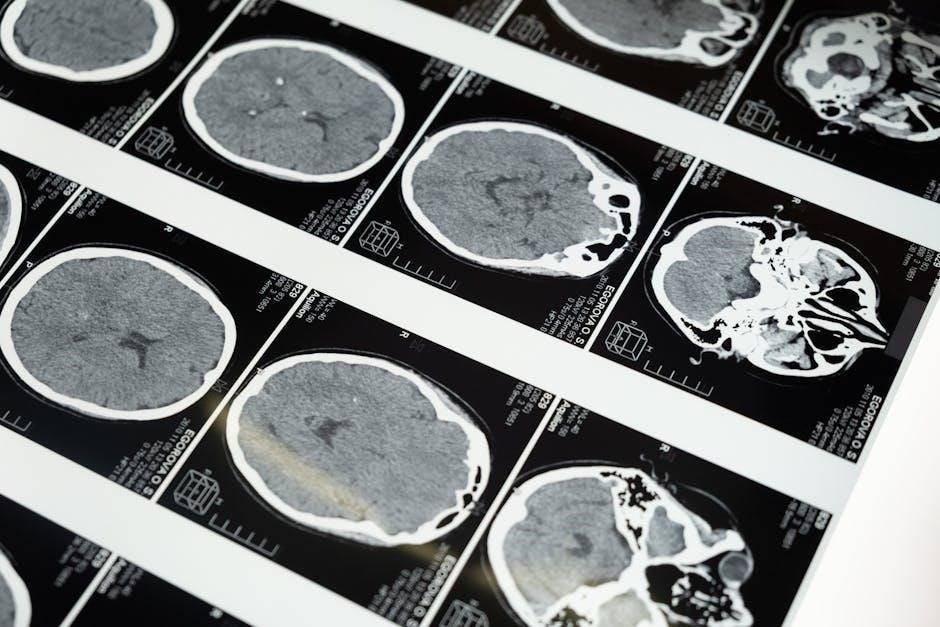

4.3 Neurological and Developmental Assessment

Neurological and developmental assessment in children is crucial for identifying abnormalities in brain function, motor skills, and developmental milestones. The examination includes evaluating mental status, cranial nerves, motor function, reflexes, and sensory responses. Developmental assessment focuses on gross and fine motor skills, language, and social interactions. Red flags include developmental delays, abnormal posturing, or loss of previously acquired skills. A systematic approach ensures comprehensive evaluation, guiding early intervention and management. This section provides practical techniques for assessing neurological and developmental status in children, aiding clinicians in identifying potential issues and improving patient outcomes through timely and appropriate care.